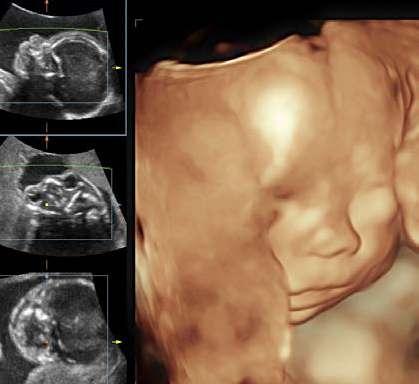

La idea de realizar ultrasonido 3D en obstetricia nació con el objetivo de visualizar estructuras anatómicas. El Dr. Tanaka a principios de 1980 quiso reconstruir y visualizar planos sagitales y coronales a partir de imágenes adquiridas en plano transversal, permitiendo ratificar la ubicación y expansión de la placenta, así como también observar con mayor claridad al feto.

La utilidad o incorporación de la ecografía 3D en la práctica clínica va más allá de un tema visual de imágenes atractivas. En obstetricia se han propuesto beneficios potenciales de la ecografía en 3D, que incluyen: (1) la capacidad de revisar datos volumétricos interactivamente, (2) la posibilidad de utilizar diferentes planos de sección para evaluar estructuras anatómicas, (3) la posibilidad de rotar la imagen volumétrica para examinarse desde diferentes perspectivas, (4) la precisión

La neurosonografía fetal se centra en la evaluación del desarrollo del cerebro desde la vida en el útero y busca la identificación de anomalías. Para poder realizar este examen se necesita buena precisión y comprensión de la neuroanatomía fetal, así como también la habilidad de interpretar y realizar planos ecográficos en 2D y 3D.

La ecografía en 3D ha sido utilizada desde principios de la implementación de la ecografía diagnóstica. El proceso de convertir imágenes 2D en 3D o 4D (3D en movimiento o también llamada 3D en tiempo real)”

La ecografía 3D y 4D para la valoración de la cara fetal cada vez interesa más detectar alteraciones como el labio, paladar hendido, y algunas malformaciones faciales relacionadas con fenotipos de trastornos genéticos subyacentes. Algunos autores han utilizado imágenes en 3D de rostros fetales para identificar de forma temprana alteraciones genéticas analizando la mandíbula, el hueso frontal y la nariz. Así mismo, se documentó que los movimientos fetales y las expresiones de la cara presentaban correlación con la actividad cerebral fetal y su estado de desarrollo (parpadear, morder la boca, sonreír y bostezar).